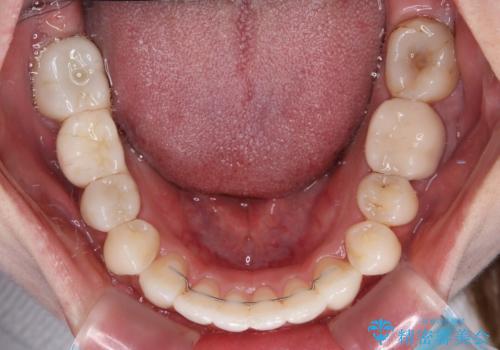

ワーキングホリデー前にきれいな歯列に

- 2、3年後にワーキングホリデーで海外に行くため、その前に歯列やむし歯をきれいにしたいとのことで来院された患者様です。

抜歯の必要な右上の奥歯は事前に抜歯をし、インビザラインにて上下歯列を整えることとしました。

矯正治療後半に奥歯の補綴治療が必要な歯にはオールセラミッククラウンを装着し、インビザラインで最終的に仕上げることとしました。

海外に行く前に口腔内環境を整えることができ、患者様には大変満足していただきました。